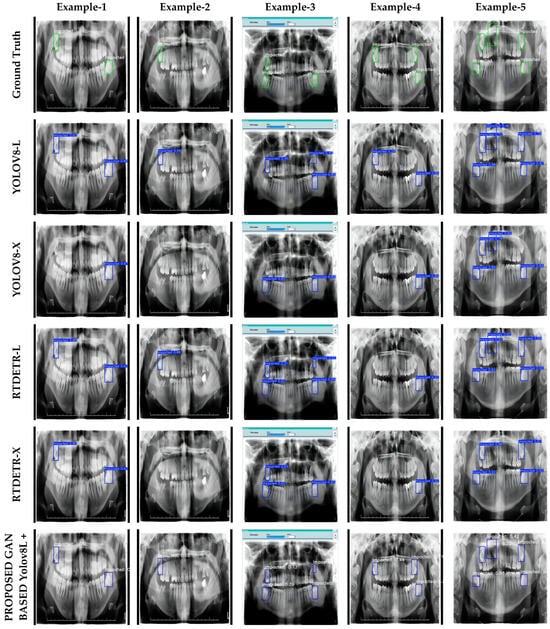

3.4. Visualization

In this study, the visual results of YOLOv8-L, YOLOv8-X, RT-DETR-L, RT-DETR-X, and the proposed GAN-based optimization-assisted ensemble model are presented in detail in Figure 3. Figure 3 contains a series of panoramic images that visually compare the performance of the models used in the impacted tooth detection task. Each column represents a specific sample panoramic image, while each row shows the predictions of different model combinations. This structure allows a visual evaluation of the detection accuracy of the models. The first row contains the actual detections (ground truth), marked with green boxes, which are used as a reference to assess the accuracy of other models. Between the second and fifth rows, the predictions of the YOLOv8-L, YOLOv8-X, RT-DETR-L, and RT-DETR-X models are shown in blue boxes. The results in these rows show how the base models perform in different situations. The last row shows the predictions of the GAN-assisted RT-DETR-L and the proposed GAN-based optimization-assisted ensemble models. These results are included to highlight the effectiveness of the proposed method compared to other models. The visualizations provide a visual verification of the numerical results in Table 4 and clearly show the performance differences of the models.

Figure 3.

Visual estimation results obtained from experimental studies.

The visualizations in Figure 3 clearly show how the embedded tooth detection performance of the proposed models responds to different scenarios. In particular, the optimized super-resolution GAN-based YOLOv8L + RT-DETR-L model showed an overall superior accuracy. The model correctly detected the vast majority of impacted teeth in all cases; however, in case 3, it incorrectly classified a non-impacted region as impacted. While this does not detract from the overall success of the model, it does suggest that further improvements are needed to reduce false positive predictions. In addition, the GAN-based YOLOv8L + RT-DETR-X model showed balanced performance, but was only able to correctly detect two of the three impacted teeth in Sample-4. This suggests that the model may occasionally have difficulty detecting impacted teeth in low-contrast regions or small sizes. However, considering the overall accuracy and precision of the model, it can be said that it provides a highly effective alternative for detecting impacted teeth.

On the other hand, the individual models YOLOv8-L, YOLOv8-X, RT-DETR-L and RT-DETR-X generally lagged behind the proposed GAN-based models. These models were found to under-detect, mis-locate or make false positive predictions in many cases. For example, these models failed to accurately localize target objects, particularly in low contrast areas or in complex panoramic images where impacted teeth overlap with other teeth. It was also found that in some cases, non-impacted teeth were incorrectly identified as impacted due to the model’s limited contextual understanding. This highlights the potential limitations of individual models in deep learning-based detection tasks and emphasizes the need for more advanced algorithms in complex image scenarios. Nevertheless, the fast processing capacity of individual models and their accuracy in certain situations suggest that they may be useful in lower cost and specific applications. However, in terms of overall performance, the integration of these models with the proposed GAN-based approaches provides significant improvements in terms of accuracy and reliability.

In conclusion, the visualizations presented in Figure 3 show that the proposed GAN-based models provide a significant advantage in terms of overall accuracy, precision and reliability compared to the individual models. However, addressing and improving the limitations observed in these models will contribute to obtaining more comprehensive and reliable results in clinical applications such as impacted tooth detection.